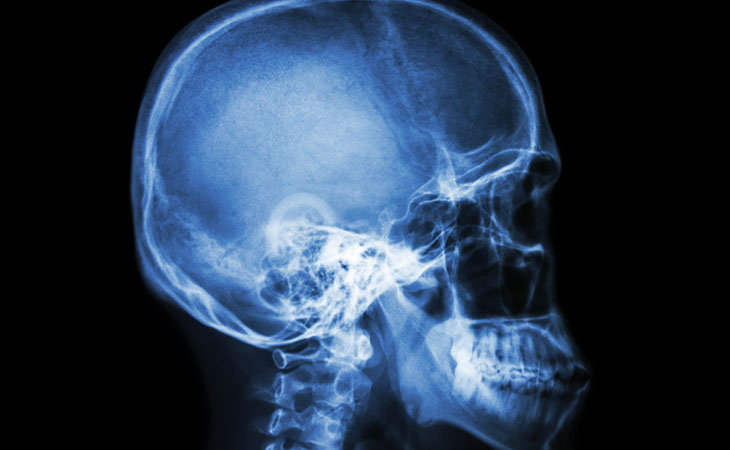

Rx cranio e seni nasali

L'rx cranio e seni nasali è un esame diagnostico che utilizza i raggi X e si esegue per lo studio della teca cranica e dei seni paranasali.

L'rx cranio e seni nasali consente di ottenereun'immagine in "bianco e nero" in cui i tessuti più densi appaiono chiari e quelli meno densi appaiono scuri, con diverse sfumature di grigio.

Il cranio è formato dalle ossa del capo, suddivise in due gruppi (ossa della scatola cranica, che contiene l'encefalo ed ossa della faccia).

I seni paranasali sono cavità delle ossa della faccia che comunicano con le fosse nasali.